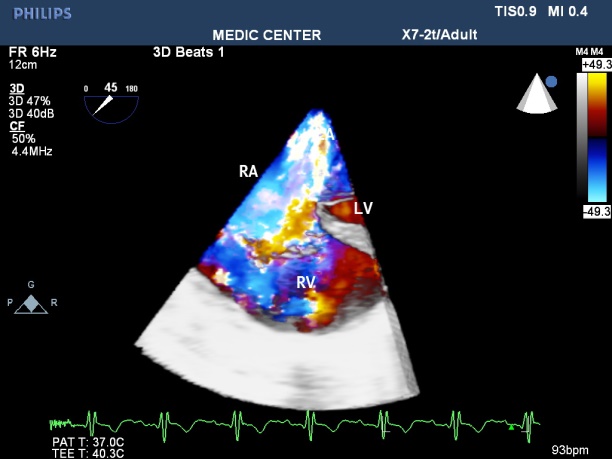

Figure 2. LAX view showing MS with severely calcified mitral leaflets& presence of LA thrombus

Figure 29. Multibeats live mode with color fow mapping visualizes the L-R shunt